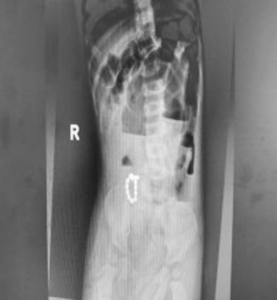

1.患儿:李某某,性别:男,年龄:2岁;简要病史:2岁男孩,因间断腹痛5天,发现消化道异物1天入院。5天前患儿无明显诱因出现腹痛,家长未予特殊重视,1天前患儿出现呕吐伴便秘,就诊于当地医院,行腹部X线片提示消化道异物(磁力球?),遂急诊就诊于我院,诊断“消化道异物(磁力球?)”收住我科。发病后患儿精神食欲差,予以开塞露后排大便1次,小便正常。既往身体健康,无家族遗传病史,心肺腹查体无异常。初步诊断:消化道异物(磁力球?)接下来,患儿需要做什么检查呢?是继续观察自行排出?还是内镜下取出?又或是剖腹探查取出呢?完善腹部X片 (两次间隔时间6小时)显示:磁力球位置未见明显变化(如下图),拟行手术治疗,手术方式为:剖腹探查术。手术探查示 (如下图):胃大弯处可见有2处直径约0.5cm穿孔 (穿孔内取出磁力球5颗),距屈氏韧带约40cm肠管近系膜侧可见2处直径约0.5cm穿孔 (穿孔内取出磁力球10颗),抗菌薇乔全层间断缝合一层胃大弯及小肠肠管穿孔,间断浆肌层加固一层;查无漏气漏液现象,吻合口直径通过顺畅。术毕。术后治疗:予以抗感染、肠外营养、过渡饮食对症治疗,患儿恢复顺利,康复出院。2.患儿:贾某某,性别:男,年龄:1岁10个月;简要病史:1岁10个月男孩,因精神反应欠佳伴烦躁哭闹4天入院。患儿于入院近4天精神反应欠佳,烦躁、哭闹,手捂腹部,呕吐2次,就诊于卫生所予以腹部外敷药物治疗,效果欠佳,后就诊于妇幼保健院,行腹部X片检查,提示消化道异物,自发病以来精神可,食欲欠佳,大便1次,小便量少。既往身体健康,无家族遗传病史,心肺腹查体无异常。初步诊断:消化道异物(磁力球?)完善腹部X片(两次间隔时间6小时)显示:磁力球位置未见明显变化(如下图),拟行手术治疗,手术方式为:剖腹探查术。手术探查示(如下图):距屈氏韧带约30cm小肠有2处直径约0.5cm穿孔(穿孔内取出磁力球1颗、螺丝1颗),距肛门口20cm处乙状结肠近系膜侧可见2处直径约0.5cm穿孔 (穿孔内取出磁力球9颗),据回盲部40cm处小肠系膜可见2处直径约0.5cm穿孔。术后治疗:予以抗感染、肠外营养、过渡饮食对症治疗,患儿恢复顺利,康复出院。